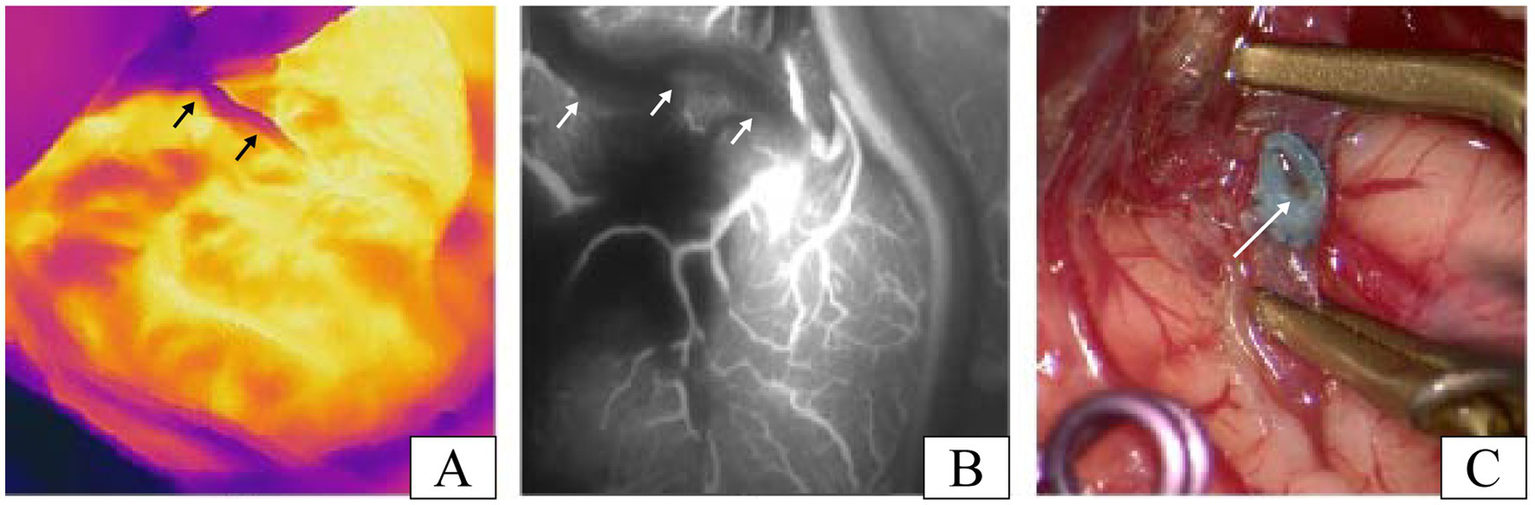

Unexpectedly, in one patient, we suspected inadequate patency after testing the anastomosis with infrared thermography, and the results of ICG-VA evaluation of the anastomosis confirmed that there was indeed an anastomotic obstruction (Figures 4A,B). After opening the anastomosis, it is obvious from Figure 4C that intravascular thrombosis was the exact cause of the anastomotic opacity in this case. This further proved the surprisingly consistent results of infrared thermography and ICG-VA in assessing anastomotic patency. The case was subsequently re-anastomosed by removing the anastomotic thrombus. Three patients developed transient neurological deterioration after surgery, including aphasia in two cases and contralateral limb asthenia in one case. Patients with these symptoms gradually resolved within 5–7 days postoperatively, and none of them experienced permanent neurological deterioration. All patients had a disappearance or improvement of transient cerebral ischemic symptoms during the follow-up period.

Figure 4

A patient with inadequate patency of vascular anastomosis in our study. (A) Infrared thermographic results of this patient after the release of the vascular clip (the black arrows denote the STA). (B) Image results of the ICG-VA after the release of the vascular clip in this patient (the white arrows indicate the STA). (C) Thrombosis was found after reopening the recipient artery and was the cause of the insufficient patency of the vascular anastomosis in this case (the white arrow shows the thrombosis in anastomosis).